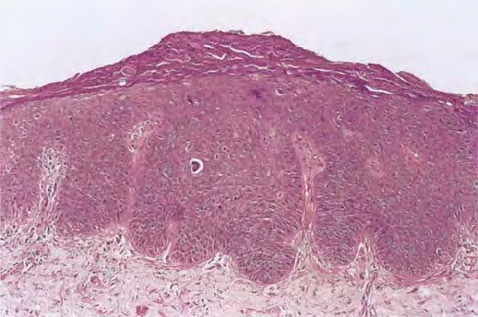

Squamous Cell Carcinoma = الكارسينوما شائكة الخلايا